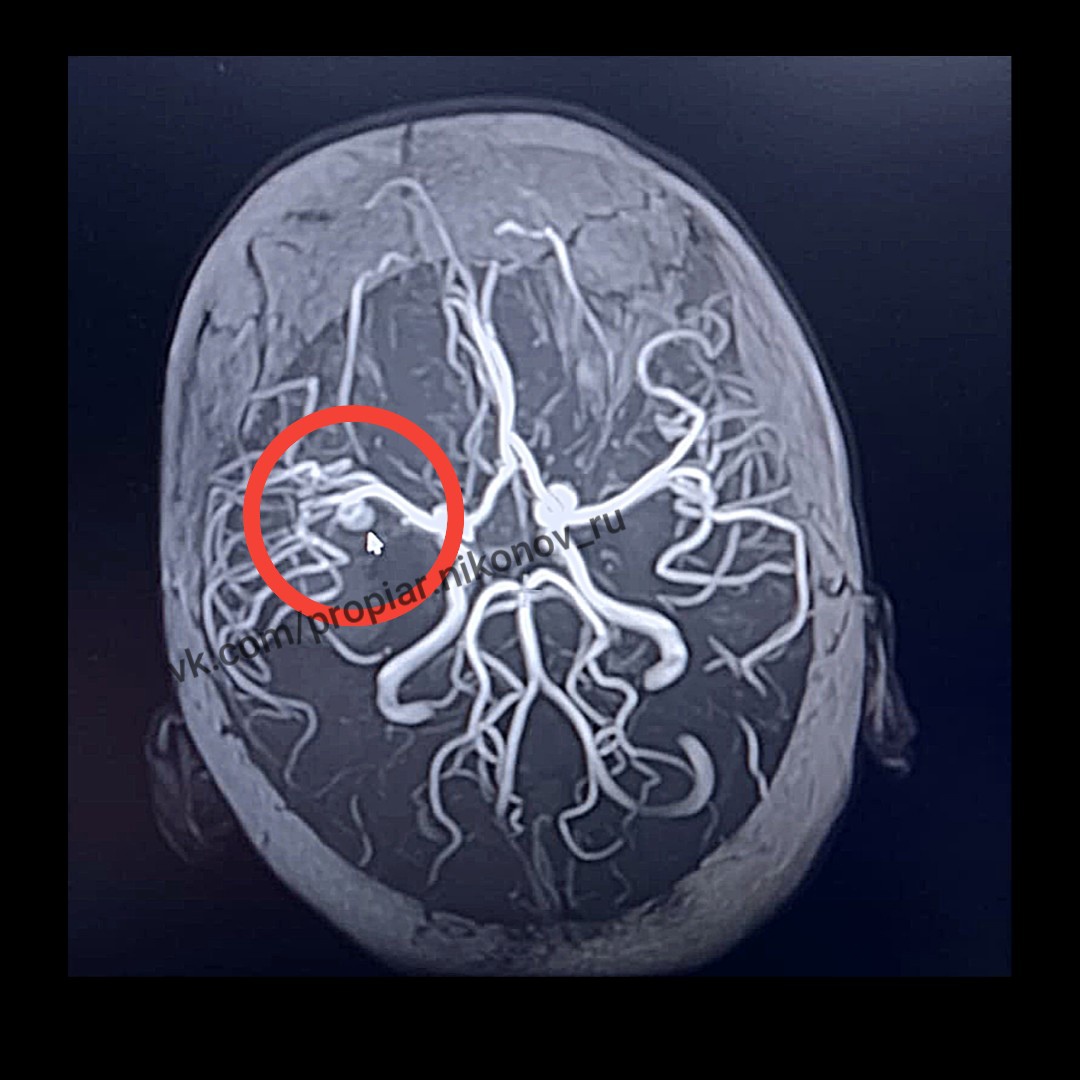

Медики сразу заподозрили аневризму головного мозга, но на операционном столе их ждал «сюрприз» — жизнеугрожающих аневризмы оказалось две, а не одна.

«К бригаде медиков НОДКБ присоединился сосудистый нейрохирург Городской клинической больницы №13 Анатолий Шелудяков, он выполнили клипирование – на шейку аневризмы средней мозговой артерии наложена специальная клипса, таким образом патологический участок исключается из общего кровотока», — поделился подробностями сотрудник пресс-службы ННГУ Алексей Никонов.